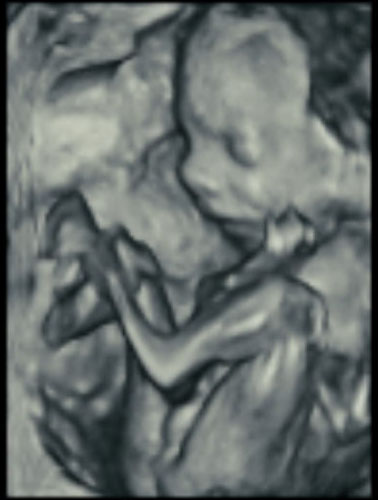

Most hospitals offer some 3D scanning, but 3D ultrasound produces images that show the width, height and depth of a developing child. Rather than sending sound waves straight into the womb and recording when they bounce back as is common in 2D imaging, 3D ultrasound sends sound waves from different angles. A computer then renders a 3D image based on this data.

4D ultrasound adds movement as it occurs. The fourth dimension is time. You’re actually watching your baby live in 3D mode. How cool is that?